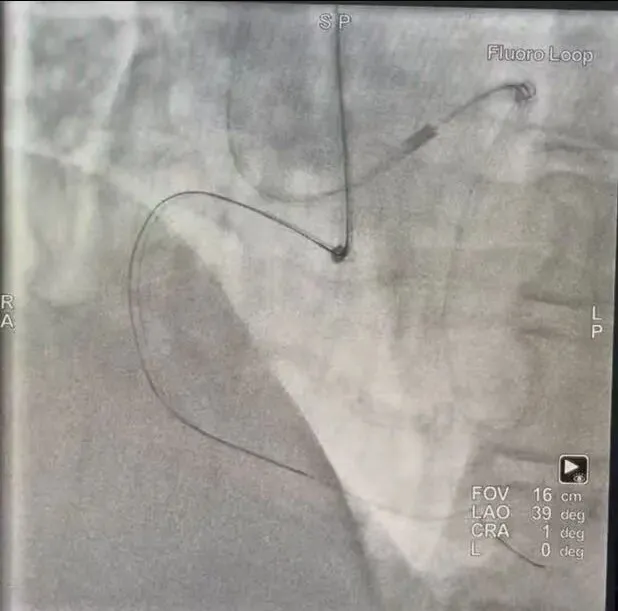

一周前,王大爷入院复查,经冠脉造影显示:之前回旋支植入支架良好,其右冠闭塞处没有残端,闭塞处又分支血管,闭塞段长且伴中重度钙化。通过双侧造影,发现前降支有两处侧枝循环逆向给右冠供血,但这种血管非常微小,逆向治疗难度大、风险高,可患者本人及家属仍有强烈手术意愿。

经南郑区人民医院心内二科介入团队充分评估及术前推演,制定了精准手术方案。9月23日上午,该科医疗团队密切配合,通过介入手术,在先处理好前降支血管后,借助这一微小的侧枝血管,将导丝及导管送到闭塞段远端,经多次尝试,运用最新的RPR策略,成功开通右冠。